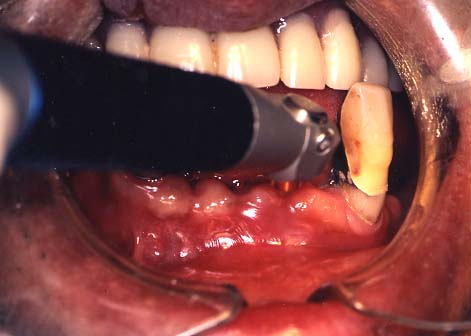

(3)口内炎

1.白く口内炎が出来ています。

さわると痛く,食べるとしみます。

2.CO2レーザーを照射しています。